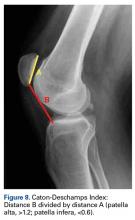

Figure 8.